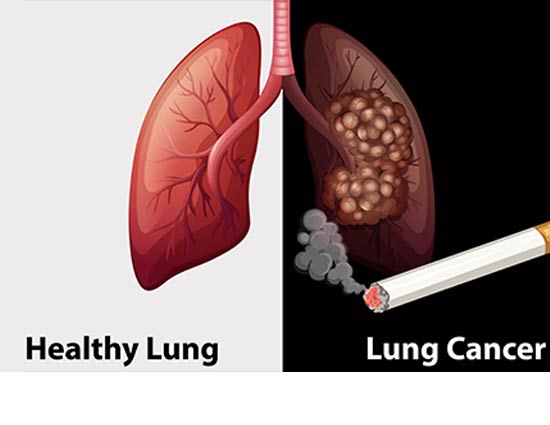

फेफड़े हमारे शरीर का एक महत्वपूर्ण अंग है जिसके बिना हमारा जीवित रहना असंभव है क्योंकि इसका काम हवा से ऑक्सीजन को अलग करके रक्त में पहुंचना होता है। हमारे शरीर से कार्बन डाईऑक्साइड पैदा होती है, जो फेफड़ों के द्वारा शरीर से आसानी से बाहर निकल जाती है। लेकिन कई बार हमारे शरीर में संक्रमण होने लगता है। जिसके कारण हमारे फेफड़े सही से काम नहीं करते और खराब होने लगते हैं। जो फेफड़े के कैंसर का रूप धारण कर लेते हैं।यह बीमारी आजकल बहुत ही ज्यादा बढ़ गयी है जिससे कई लोग ग्रसित होते है। यह समस्या पुरुष या महिला दोनों में से किसी को भी हो सकती है। तो आइये जानते है इसके लक्षण, कारण और बचाव के बारे में.....

# कारण

धुम्रपान और शराब का सेवन